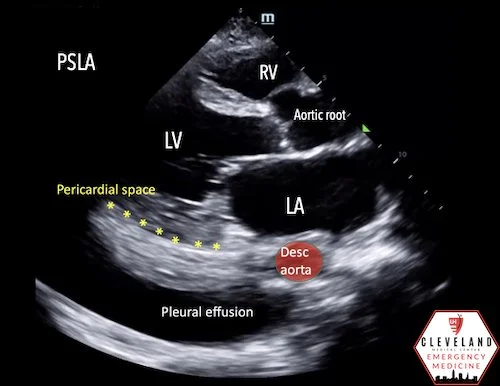

• Differentiate from pleural effusion by looking at its relation to descending thoracic aorta in the parasternal long axis view (why it's important to have enough depth to visualize it)

• pericardial effusion is anterior to the aorta whereas a pleural effusion goes behind/deep to aorta.